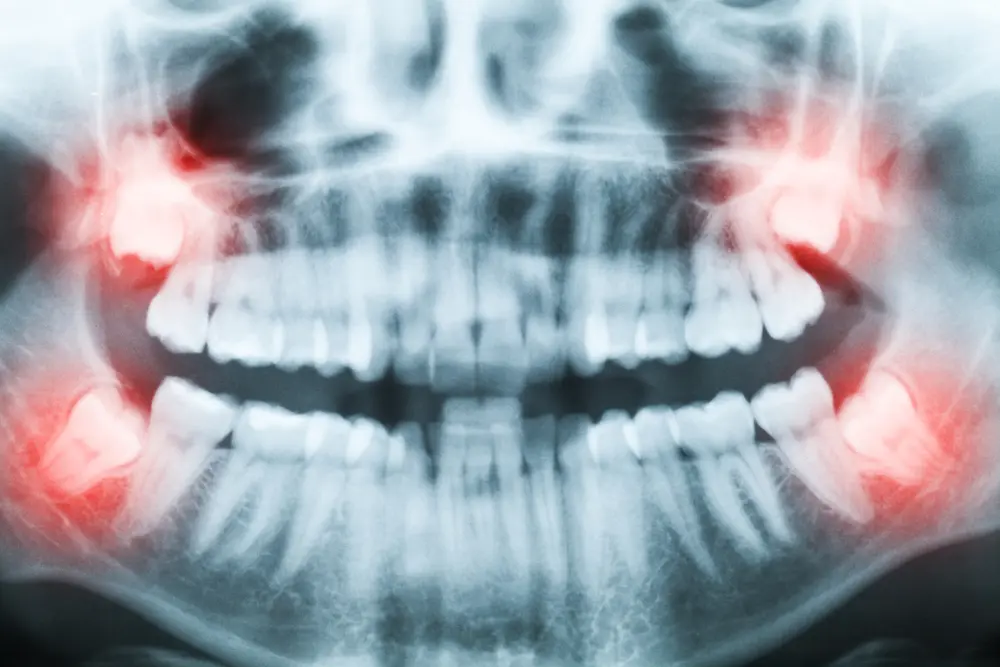

Do Wisdom Teeth Affect Braces?

At Bret Johnson Orthodontics, we care about patient concerns. A frequent question we’re asked before orthodontic treatment is: “Should I have my wisdom teeth removed, so they don’t impact my professionally straightened smile?” Similarly, other patients who have completed their orthodontic treatment may notice their wisdom teeth starting to erupt, and they wonder if these… Read more »